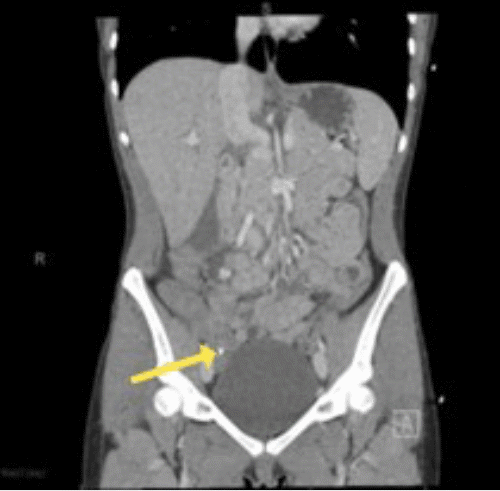

A 21-year-old female with a past medical history of asthma and a current intrauterine device (IUD) presented with sudden onset, diffuse abdominal pain associated with nausea, vomiting, and chills. The abdominal pain started about 12 hours prior and worsened throughout the day. She was afebrile and hemodynamically stable on arrival. Physical exam was significant for severe right lower quadrant tenderness with involuntary guarding. Blood tests showed an elevated white blood cell count (26,000) and mildly elevated lactic acid (3.2 mmol/L). A pregnancy test was negative. Abdominal and pelvic CT scan demonstrated a fluid-filled appendix with a fecalith obstructing the opening (appendix ostia), consistent with acute appendicitis (Figures 1 and 2). The patient received a single dose of metronidazole and levofloxacin for empiric antibiotic coverage and proceeded directly to laparoscopic appendectomy.

Figure 1. Coronal View of Abdominopelvic CT with Arrow Pointing to Fecalith at Ostia of Appendix. Published with Permission